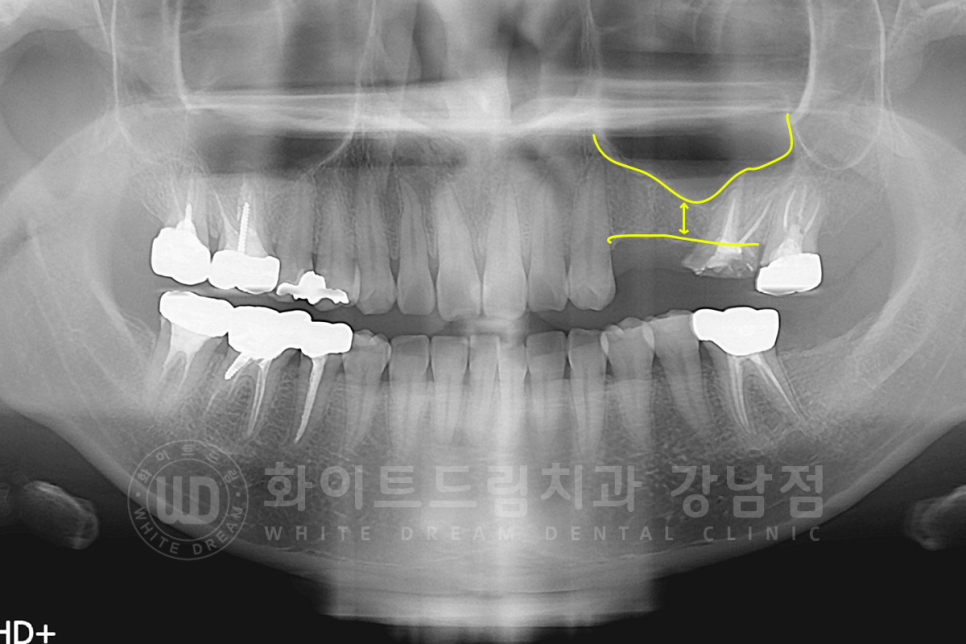

계란의 얇은 막으로 둘러싸여 있는 상악동을 들어 올려 그 사이에 잇몸뼈를 만드는 상악동 거상술은

① lateral 술식과 ② crestal 술식

두 가지로 나누어집니다.

lateral은 뺨 쪽 잇몸에 작은 창문을 내어 진행하는 술식으로

많은 양의 뼈이식을 진행할 때 진행하고 굉장히 고난도의 치료 술식입니다.

① 계란 껍데기처럼 얇은 상악동 막을 손상되지 않도록 들어 올립니다.

② 들어 올린 상악동 막 안쪽으로 임플란트가 상악동을 침범하지 않도록 넉넉하게 골 이식재를 넣습니다.

③, ④ 이식재가 잘 자리 잡았는지 확인한 후 임플란트를 식립합니다.

(케이스에 따라 동시 진행할 수도 있고, 뼈가 굳는 시간을 가진 후 임플란트 수술을 진행할 수도 있습니다.)